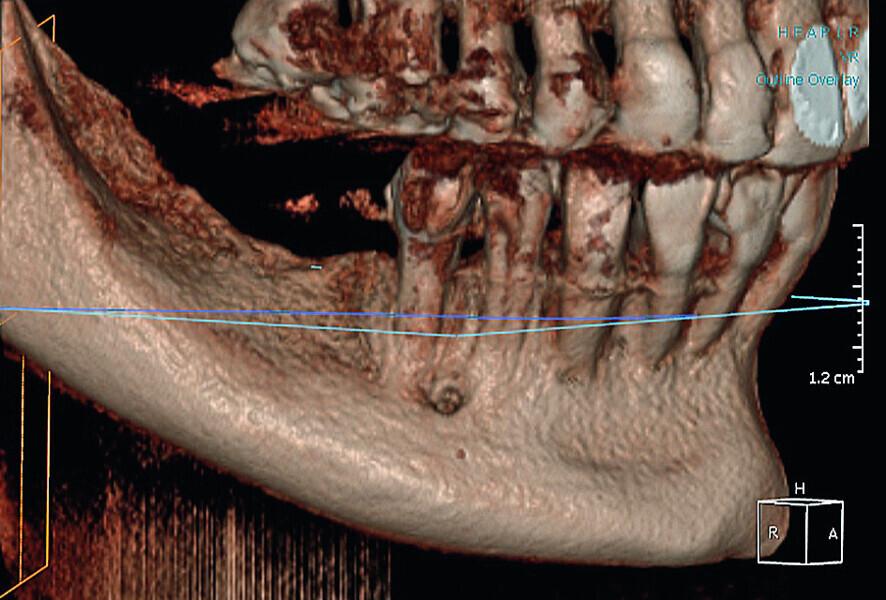

Fig. 13: CBCT reconstruction of a deficient ridge in the lateral mandible.